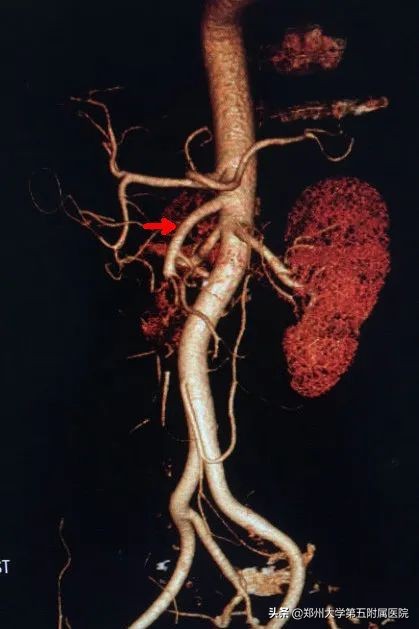

肠系膜上动脉在肾动脉的上方发自腹主动脉的前壁,沿途向左侧发出十几条肠动脉,向右侧自上而下发出胰十二指肠下动脉、中结肠动脉、右结肠动脉和回结肠动脉,它们分布于十二指肠、胰头、空肠、回肠、盲肠、阑尾、升结肠和横结肠右半,并彼此间形成吻合。可见该动脉为大部分肠道供血,如发生栓塞则可出现严重后果(图4,5)。

▲ 图4 CTA 肠系膜上动脉(白色尖头)

▲ 图5 肠系膜上动脉及主要分支

该疾病最常见的症状就是突发腹痛,伴或不伴恶心,呕吐,根据栓塞的程度和部位不同,临床症状会有差别。所以如果是一名既往存在心律失常-房颤的患者,突发腹痛,一定要考虑到急性肠系膜上动脉栓塞。最常用的检查就是腹部彩超,可以同时排除胰腺炎,胆囊炎,阑尾炎等常见的急腹症,但确诊需要CTA检查(图4)。肠道及其脆弱,一旦急性缺血很容易导致坏死,同时肠道大量菌群移位入血,导致严重的菌血症,死亡率极高。所以诊断要及时,一旦明确诊断,手术取栓是首选治疗方案,同时术中可以探查肠管如果合并坏死,可一并切除。